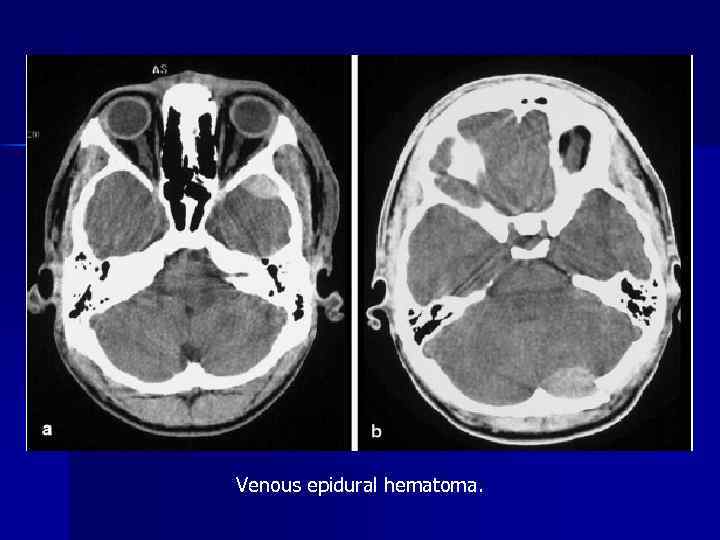

Venous epidural hematoma.